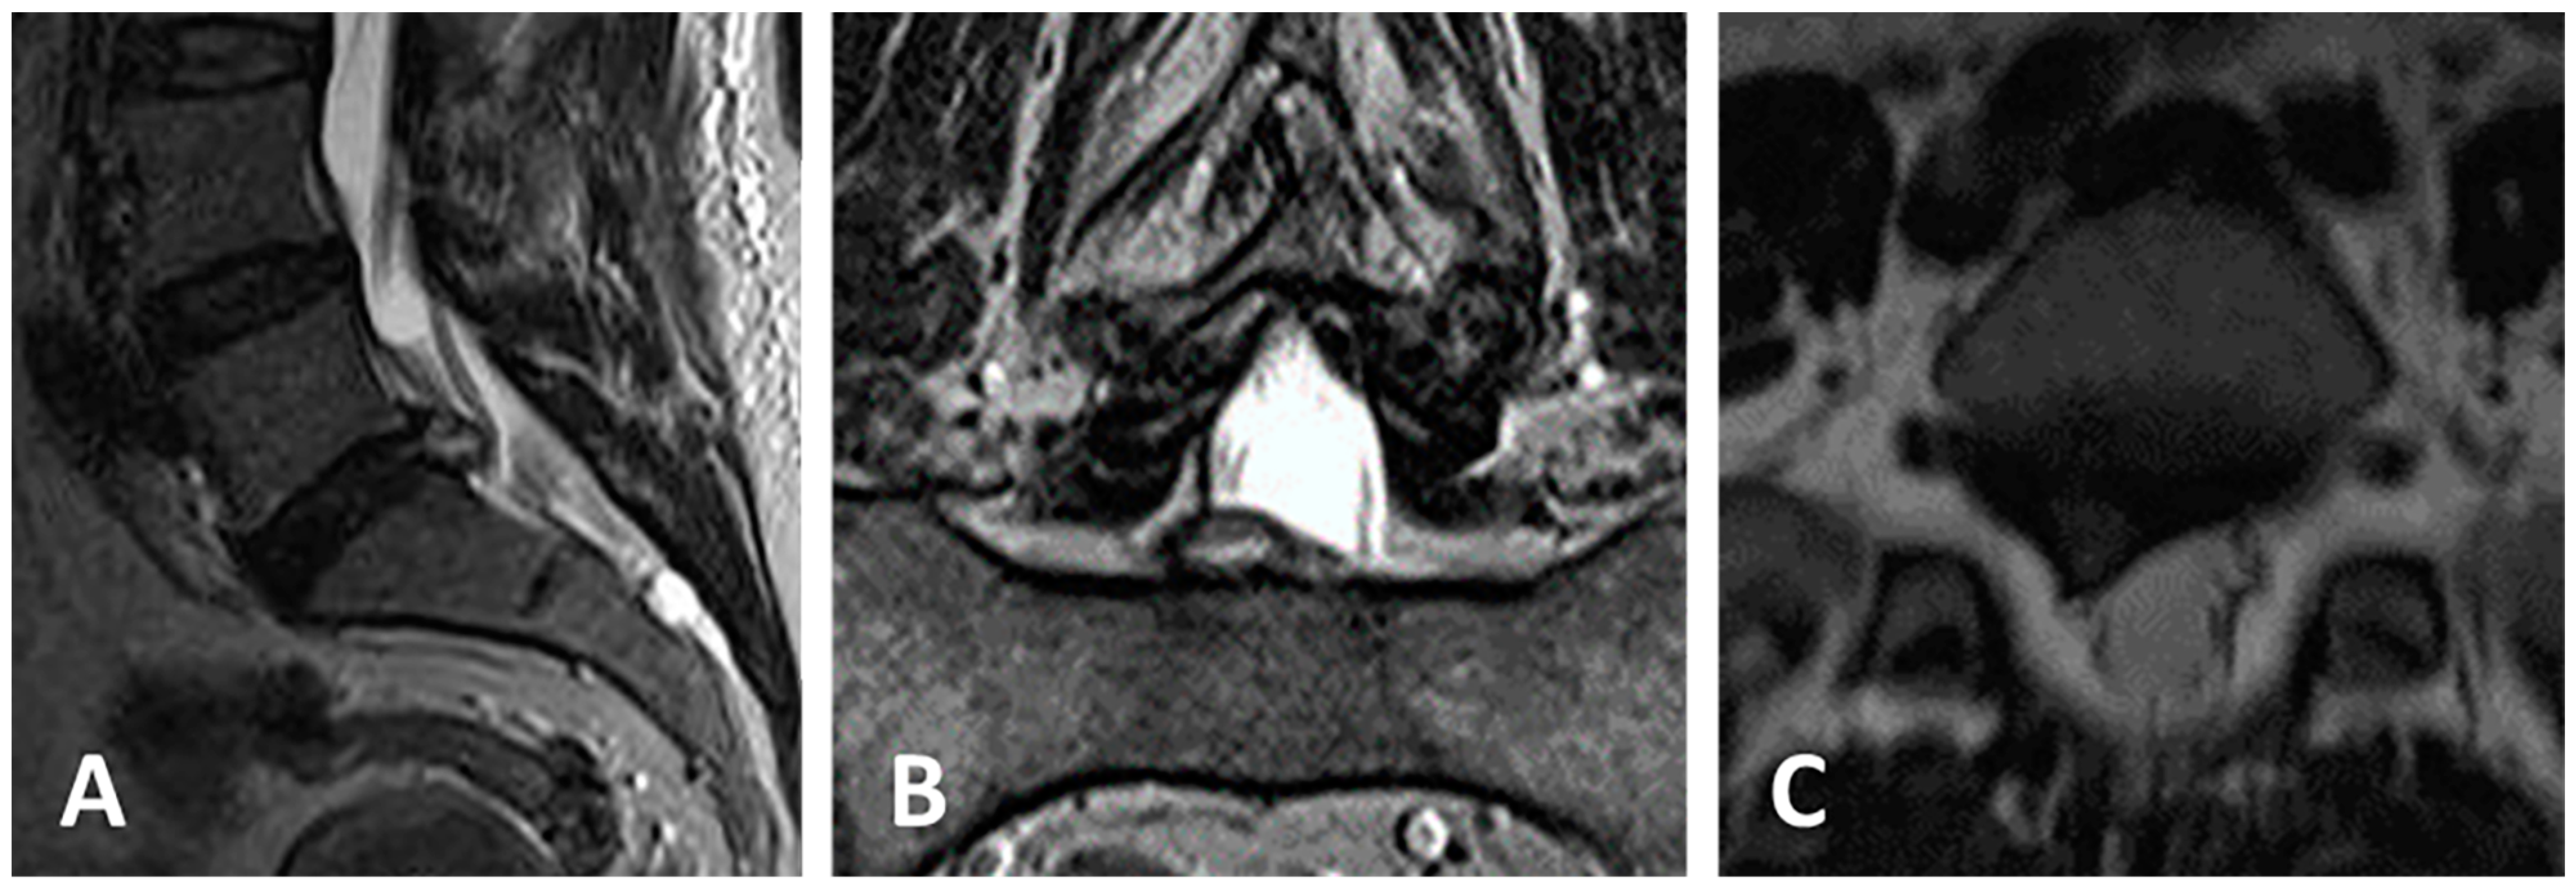

3.4. Clinical Case 2